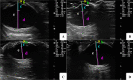

Background: Environmental changes contribute to the development of ophthalmic diseases in sea turtles, but information on their eye biometrics is scarce. The aim of this study was to describe ophthalmic ultrasonographic features of four different sea turtle species; Caretta caretta (Loggerhead turtle; n = 10), Chelonia mydas (Green turtle; n = 8), Eretmochelys imbricata (Hawksbill turtle; n = 8) and Lepidochelys olivacea (Olive ridley; n = 6) under human care. Corneal thickness, scleral ossicle width and thickness, anterior chamber depth, axial length of the lens, vitreous chamber depth and axial globe length were measured by B-mode sonography with a linear transducer. Carapace size and animal weight were recorded. A sonographic description of the eye structures was established.

Results: The four species presented an ovate eyeball, a relatively thin cornea, and a small-sized lens positioned rostrally in the eye bulb, near the cornea, resulting in a shallow anterior chamber. The scleral ossicles did not prevent the evaluation of intraocular structures, even with a rotated eye or closed eyelids; image formation beyond the ossicles and measurements of all proposed structures were possible. B-mode sonography was easily performed in all animals studied. The sonographic characteristics of the eye were similar among the four species. Since there was a correlation between the size of the eye structures and the size of the individual, especially its carapace size, the differences found between E. imbricata and Caretta caretta are believed to be due to their overall difference in size.